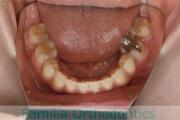

下の前歯が後ろにあるのが気になるとのことで来院されました。非抜歯で行うことも可能でしたが、上下左右から小臼歯抜歯をして治療を行うことをご希望になりました。

マルチブラケット法にて治療を行い、約3年、40回の通院が要でした。

かみ合わせが深い(上の前歯で下の前歯が覆われてしまう)ので、保定をしっかりしないと、また深くなってきてしまいやすいです。

上顎

下顎

前歯の関係など